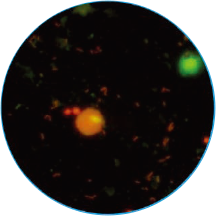

免疫荧光法结果展示及判读示例

阴道分泌物多重免疫荧光染色技术,具备形态学与荧光学的双重优势。可以同时对上皮细胞,白细胞,乳酸杆菌,线索细胞,念珠菌和毛滴虫等进行染色区分,既能检测阴道相关病原体感染,也能评估其阴道微生态和阴道清洁度等是否正常,为临床的快速诊断和治疗提供帮助。

念球菌

橙红色荧光

孢子形态直径3-6 μm

明显大于细菌,小于滴虫